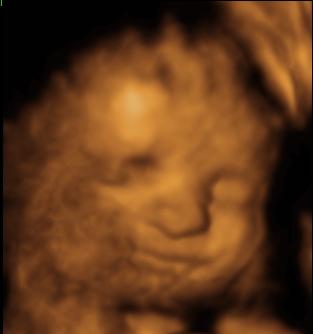

Nem raksz fel Ádiról 4D-s képet, hogy berakhassam?! Még mielőtt kibújna.

"Csupasz" pocak 36+4 (Ne ijedjetek meg!!):